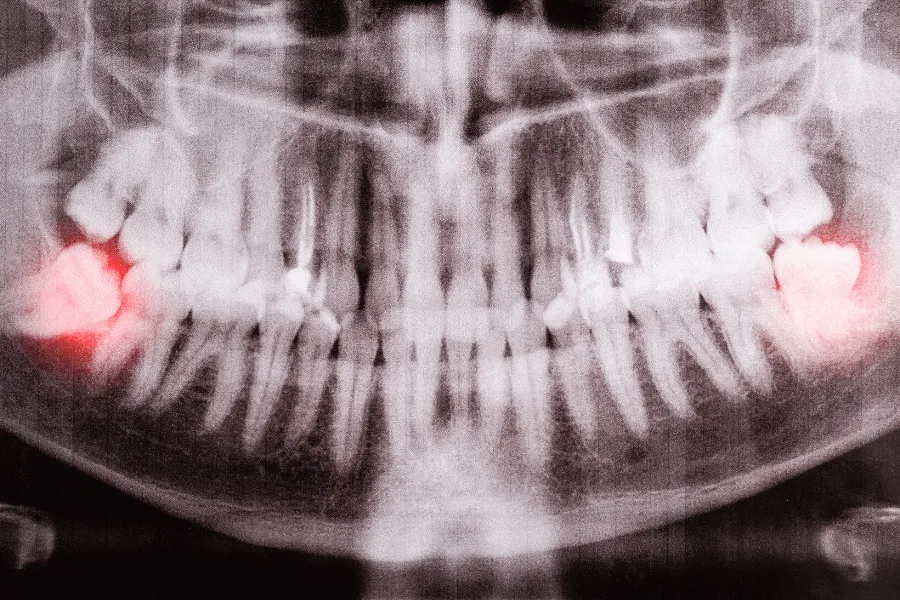

Zatrzymana ósemka (położona poziomo, skośnie, głęboko) uciskająca siódemkę lub powodująca torbiel/ubytki.

W Dental Wilanów decyzję podejmujemy po badaniu klinicznym i obrazie RTG; przy skomplikowanej anatomii korzeni lub bliskości nerwu wykonujemy CBCT 3D.

Kwalifikacja – wywiad, badanie, RTG; przy zatrzymanych ósemkach często zalecamy CBCT, by ocenić położenie korzeni i przebieg nerwu.

Zatrzymana ósemka a CBCT – kiedy tomografia jest potrzebna

Położenie korzeni blisko nerwu zębodołowego dolnego.

Nietypowy przebieg korzeni (zakrzywienia, rozwidlenia).

Podejrzenie torbieli lub zmian w kości.

Plan jednoczesnego usunięcia kilku ósemek lub zabiegu w złożonych warunkach anatomicznych.

CBCT 3D wykonujemy na miejscu, dzięki czemu zabieg planujemy precyzyjnie i bezpiecznie.